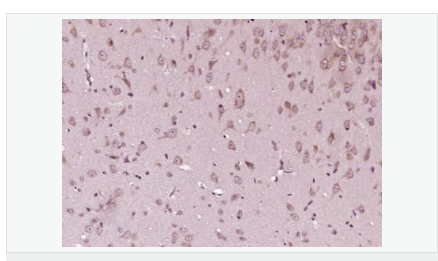

| 產(chǎn)品應(yīng)用 | WB=1:500-2000 ELISA=1:5000-10000 IHC-P=1:100-500 IHC-F=1:100-500 Flow-Cyt=1μg/Test ICC=1:100-500 IF=1:100-500 (石蠟切片需做抗原修復(fù)) not yet tested in other applications. optimal dilutions/concentrations should be determined by the end user. |

| 產(chǎn)品介紹 | This gene encodes a cyclin-dependent kinase inhibitor, which shares a limited similarity with CDK inhibitor CDKN1A/p21. The encoded protein binds to and prevents the activation of cyclin E-CDK2 or cyclin D-CDK4 complexes, and thus controls the cell cycle progression at G1. The degradation of this protein, which is triggered by its CDK dependent phosphorylation and subsequent ubiquitination by SCF complexes, is required for the cellular transition from quiescence to the proliferative state. [provided by RefSeq, Jul 2008] Function: Important regulator of cell cycle progression. Involved in G1 arrest. Potent inhibitor of cyclin E- and cyclin A-CDK2 complexes. Forms a complex with cyclin type D-CDK4 complexes and is involved in the assembly, stability, and modulation of CCND1-CDK4 complex activation. Acts either as an inhibitor or an activator of cyclin type D-CDK4 complexes depending on its phosphorylation state and/or stoichometry. Subunit: Forms a ternary compex with CCNE1/CDK2/CDKN1B. Subcellular Location: Nucleus. Cytoplasm. Endosome. Note=Nuclear and cytoplasmic in quiescent cells. AKT-or RSK-mediated phosphorylation on Thr-198, binds 14-3-3, translocates to the cytoplasm and promotes cell cycle progression. Mitogen-activated UHMK1 phosphorylation on Ser-10 also results in translocation to the cytoplasm and cell cycle progression. Phosphorylation on Ser-10 facilitates nuclear export. Translocates to the nucleus on phosphorylation of Tyr-88 and Tyr-89. Colocalizes at the endosome with SNX6; this leads to lysosomal degradation. Tissue Specificity: Expressed in all tissues tested. Highest levels in skeletal muscle, lowest in liver and kidney. Post-translational modifications: Phosphorylated; phosphorylation occurs on serine, threonine and tyrosine residues. Phosphorylation on Ser-10 is the major site of phosphorylation in resting cells, takes place at the G(0)-G(1) phase and leads to protein stability. Phosphorylation on other sites is greatly enhanced by mitogens, growth factors, cMYC and in certain cancer cell lines. The phosphorylated form found in the cytoplasm is inactivate. Phosphorylation on Thr-198 is required for interaction with 14-3-3 proteins. Phosphorylation on Thr-187, by CDK2 leads to protein ubiquitination and proteasomal degradation. Tyrosine phosphorylation promotes this process. Phosphorylation by PKB/AKT1 can be suppressed by LY294002, an inhibitor of the catalytic subunit of PI3K. Phosphorylation on Tyr-88 and Tyr-89 has no effect on binding CDK2, but is required for binding CDK4. Dephosphorylated on tyrosine residues by G-CSF. Ubiquitinated; in the cytoplasm by the KPC complex (composed of RNF123/KPC1 and UBAC1/KPC2) and, in the nucleus, by SCF(SKP2). The latter requires prior phosphorylation on Thr-187. Ubiquitinated; by a TRIM21-containing SCF(SKP2)-like complex; leads to its degradation. DISEASE: Defects in CDKN1B are the cause of multiple endocrine neoplasia type 4 (MEN4) [MIM:610755]. Multiple endocrine neoplasia (MEN) syndromes are inherited cancer syndromes of the thyroid. MEN4 is a MEN-like syndrome with a phenotypic overlap of both MEN1 and MEN2. Similarity: Belongs to the CDI family. SWISS: P46527 Gene ID: 1027 Database links: Entrez Gene: 1027 Human Entrez Gene: 12576 Mouse Omim: 600778 Human SwissProt: P46527 Human SwissProt: P46414 Mouse Unigene: 238990 Human Unigene: 2958 Mouse Important Note: This product as supplied is intended for research use only, not for use in human, therapeutic or diagnostic applications. P27蛋白是一種新發(fā)現(xiàn)的周期素依賴激酶抑制劑,屬于細(xì)胞周期的負(fù)性調(diào)控因子。P27基因及其產(chǎn)物的異常表達可能與某些腫瘤的發(fā)生、發(fā)展有著密切的關(guān)系。P27蛋白對細(xì)胞周期的調(diào)控及在腫瘤中發(fā)揮著很重要的作用。 |